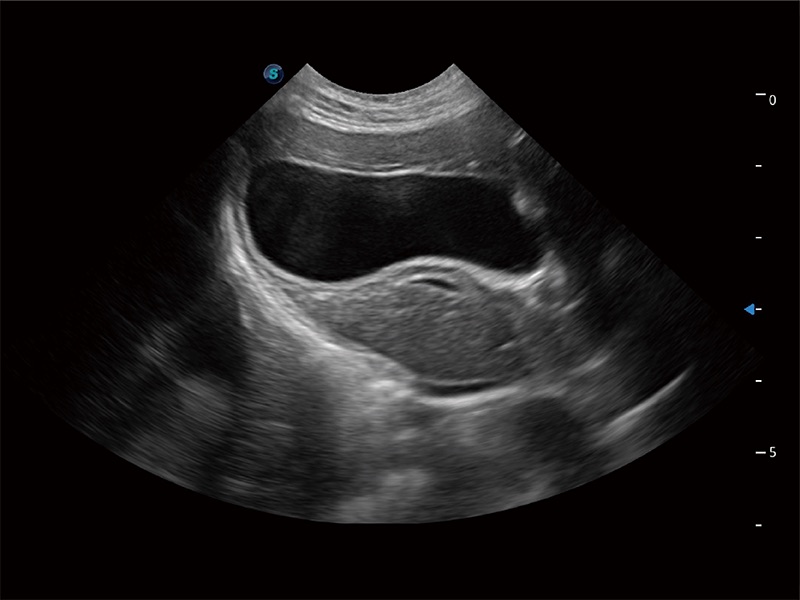

高性能和先進(jìn)的臨床應(yīng)用工具可以為動物醫(yī)生提供臨床信心。ProPet 80 搭載了先進(jìn)的腹部和淺表應(yīng)用工具,幫助醫(yī)生在日常臨床實(shí)踐中發(fā)揮前所未有的作用。

極大提升超低速微細(xì)血流的檢出能力,同時更精準(zhǔn)地濾除軟組織和超聲信號,為獸用醫(yī)生提供以往無法通過常規(guī)血流獲得的疾病診斷信息。

ProPet 80 專為動物醫(yī)生設(shè)計,對不同的動物體型和生理結(jié)構(gòu)作出了針對性的優(yōu)化。通過動物影像專用軟件,可滿足個性化的應(yīng)用需求,幫助動物醫(yī)生獲得更精確的診斷數(shù)據(jù)。

為精細(xì)結(jié)構(gòu)及組織邊緣提供高清晰度的圖像和更大的成像視野。幫助減輕醫(yī)生的用眼疲勞,快速精準(zhǔn)獲得測量的數(shù)據(jù)。